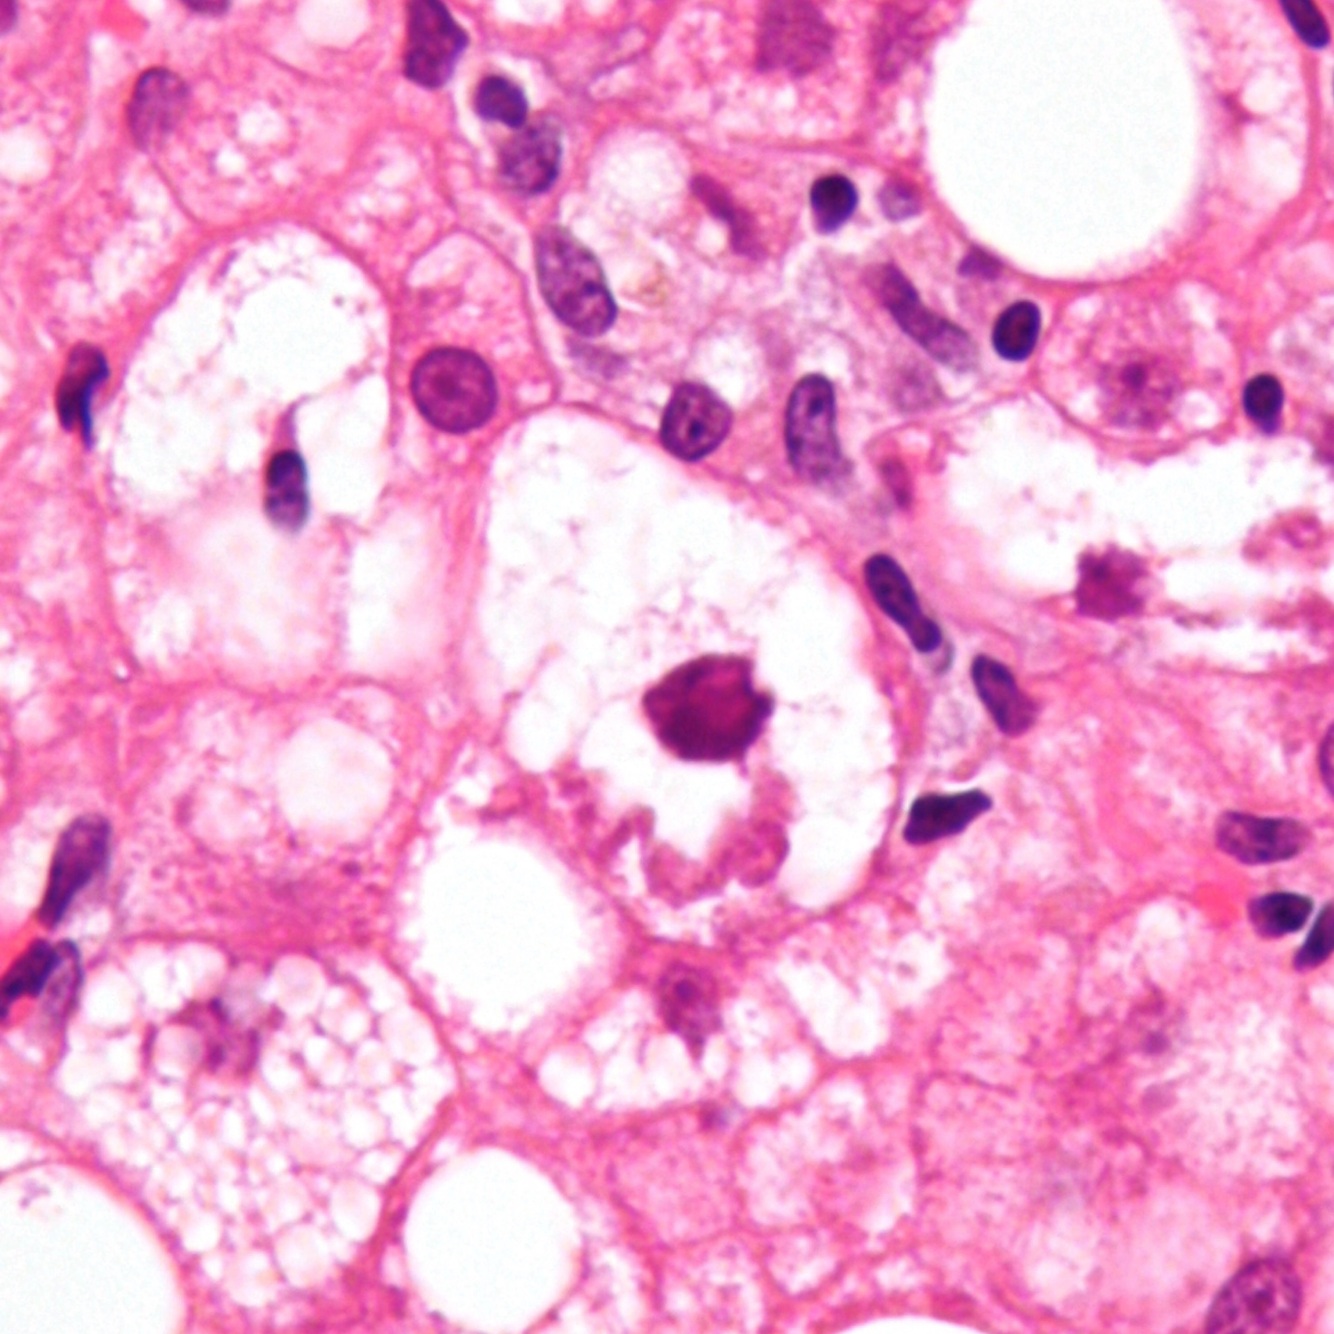

alcohol-associated hepatitis: Fatty changes (macro- and microvesicular), Mallory bodies, and a neutrophilic infiltrate

Mallory body